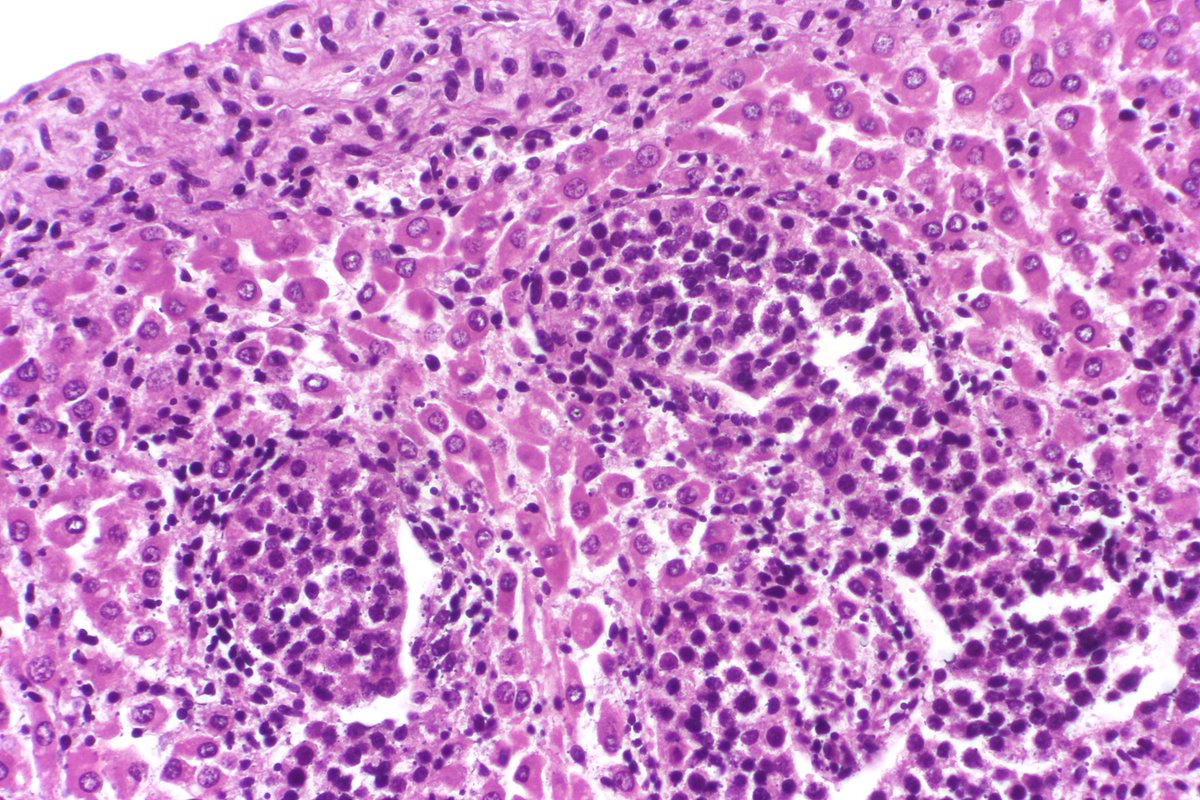

Type B2 Thymoma showing prominent large epithelial cells admixed with numerous lymphocytes. #pathology #PulmPath